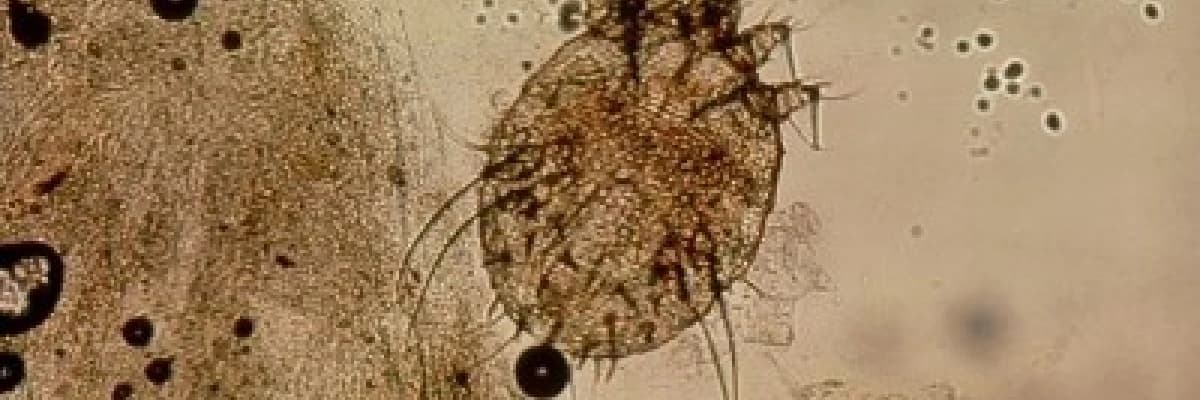

Tanı; dermatoloji hekimleri tarafından yapılan dermoskopik muayene veya deriden alınan kazıntının mikroskobik değerlendirilmesi ile yapılır.